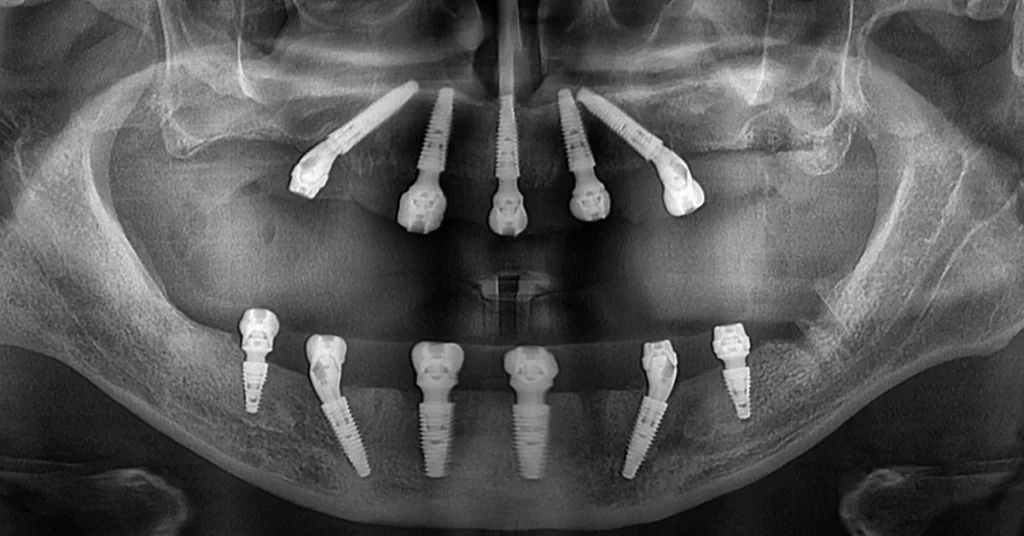

Pacientul a venit la noi cu parodontoza avansata, care a dus la pierderea dintilor si afectarea structurii osoase. Am efectuat o reabilitare completa prin inserarea a 5 implanturi la maxilar si 6 implanturi standard la mandibula. In doar 24 de ore, a primit o lucrare provizorie fixa, care a asigurat functionalitate si estetica imediata. Dupa o perioada de 6 luni de osteointegrare, s-au realizat lucrarile definitive din ceramica stratificata pe zirconiu, atat la maxilar, cat si la mandibula. Rezultatul final a restabilit o muscatura stabila, un zambet natural si o sanatate orala durabila, in ciuda situatiei initiale complexe.